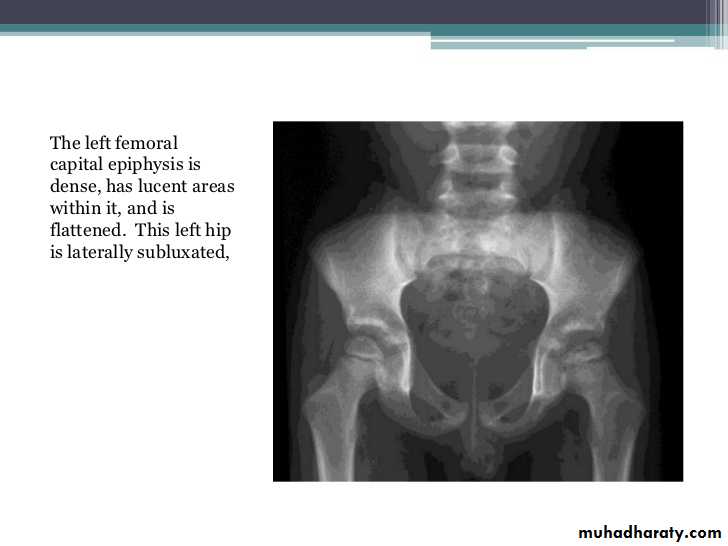

Rheumatoid Arthritis (RA)

Earliest signs include

1.soft tissue swelling due to effusion, tenosynovitis, and edema2.Symmetric Periarticular osteopenia

3.Marginal erosions often first seen at 2nd and 3rd MCPs and 3rd PIP articulations

Preferred sites of early involvement:

Hand: 2nd & 3rd MCP jointsFoot: 4th & 5th MTP joints

Late signs include:

1.Large marginal erosions have nearly destroyed the joints

2.Erosion of ulnar styloid

3.Subcondral cyst

4.Subluxation